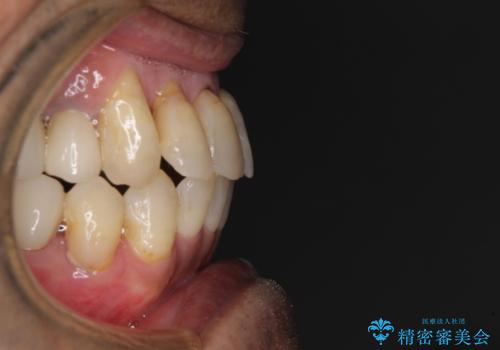

歯列不正と歯周病 総合歯科治療による全顎治療

- 前歯がのデコボコや、奥歯に咬んだときに痛みがあるとのことで来院された患者様です。

全体的に問題が多く、全てをしっかりと治療したいとのことでした。

全体的に中等度の歯周病と診断されたため、歯周外科処置やインプラントによる咬合回復から進めて行き、矯正治療による歯列改善を行った後にオールセラミッククラウンにて補綴することとしました。